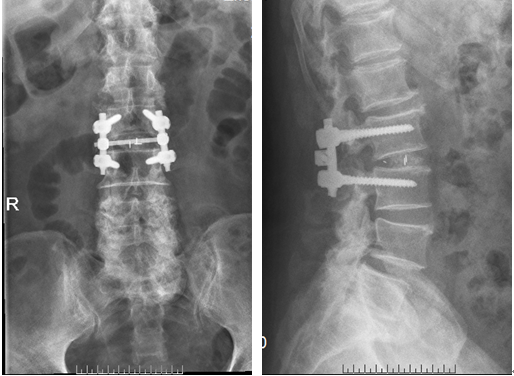

术后影像: